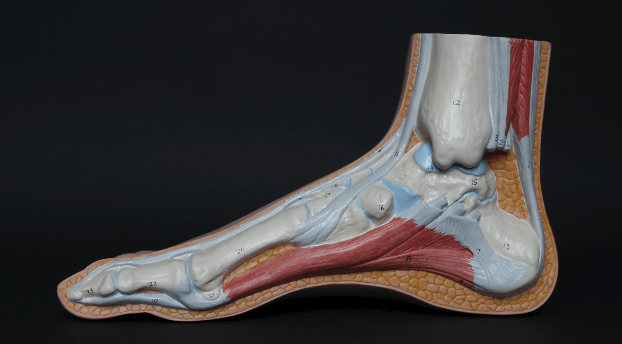

Some people are born with flat feet. By taking a look at your feet, you will be able to tell whether you were born with flat feet or not. Among people with flat feet, you will be able to see fallen arches. A healthy person will have a small arch in between the ball and the heel of the feet. However, it is not possible for you to see such an arch among people who are affected with flat feet. This is the most common symptom associated with flat feet and you should be mindful of it.

Tendon injuries are another common reason behind flat feet that people get. Therefore, it is important for you to be mindful of those injuries as well. The head bone of your body is connected to the neck bone. Likewise, it is also connected to the bones in your ankle as well. Therefore, tendon injuries can make you lose proper balance in the bones of your body and lead you to flat feet.

People who are affected with plantar fascia are having flat feet. On the other hand, tears, inflammation, and other related injuries can make the arches fall. Once that happens, you will end up getting flat feet.

Along with an injury, bones, as well as all the other connective tissues in the feet, are in a position to create an intricate network. This would facilitate the movement. On the other hand, this network is in a position to provide all support needed by your body as well. However, ending up with an injury to the ankle or foot can make you deal with flat feet and many other problems that can take place along with it.

Along with nerve damage, you will end up losing sensation in your feet. This will make the arches in your feet collapse. This is the health condition called Charcot’s foot. When the ligaments of your feet loosen, there is a possibility for the arches to fail. Along with that, it is possible for the bones to slide out of place as well. This can lead you to disintegrate and fracturing of the bones.